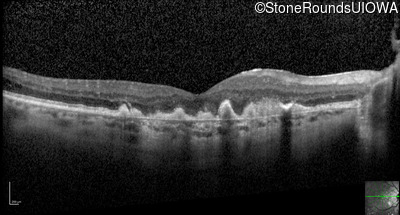

Visit at age: 60 years (Visit 3)

Optical Coherence Tomography - Right - 20/150

Exemplar / OCT Stack

OCT Stack